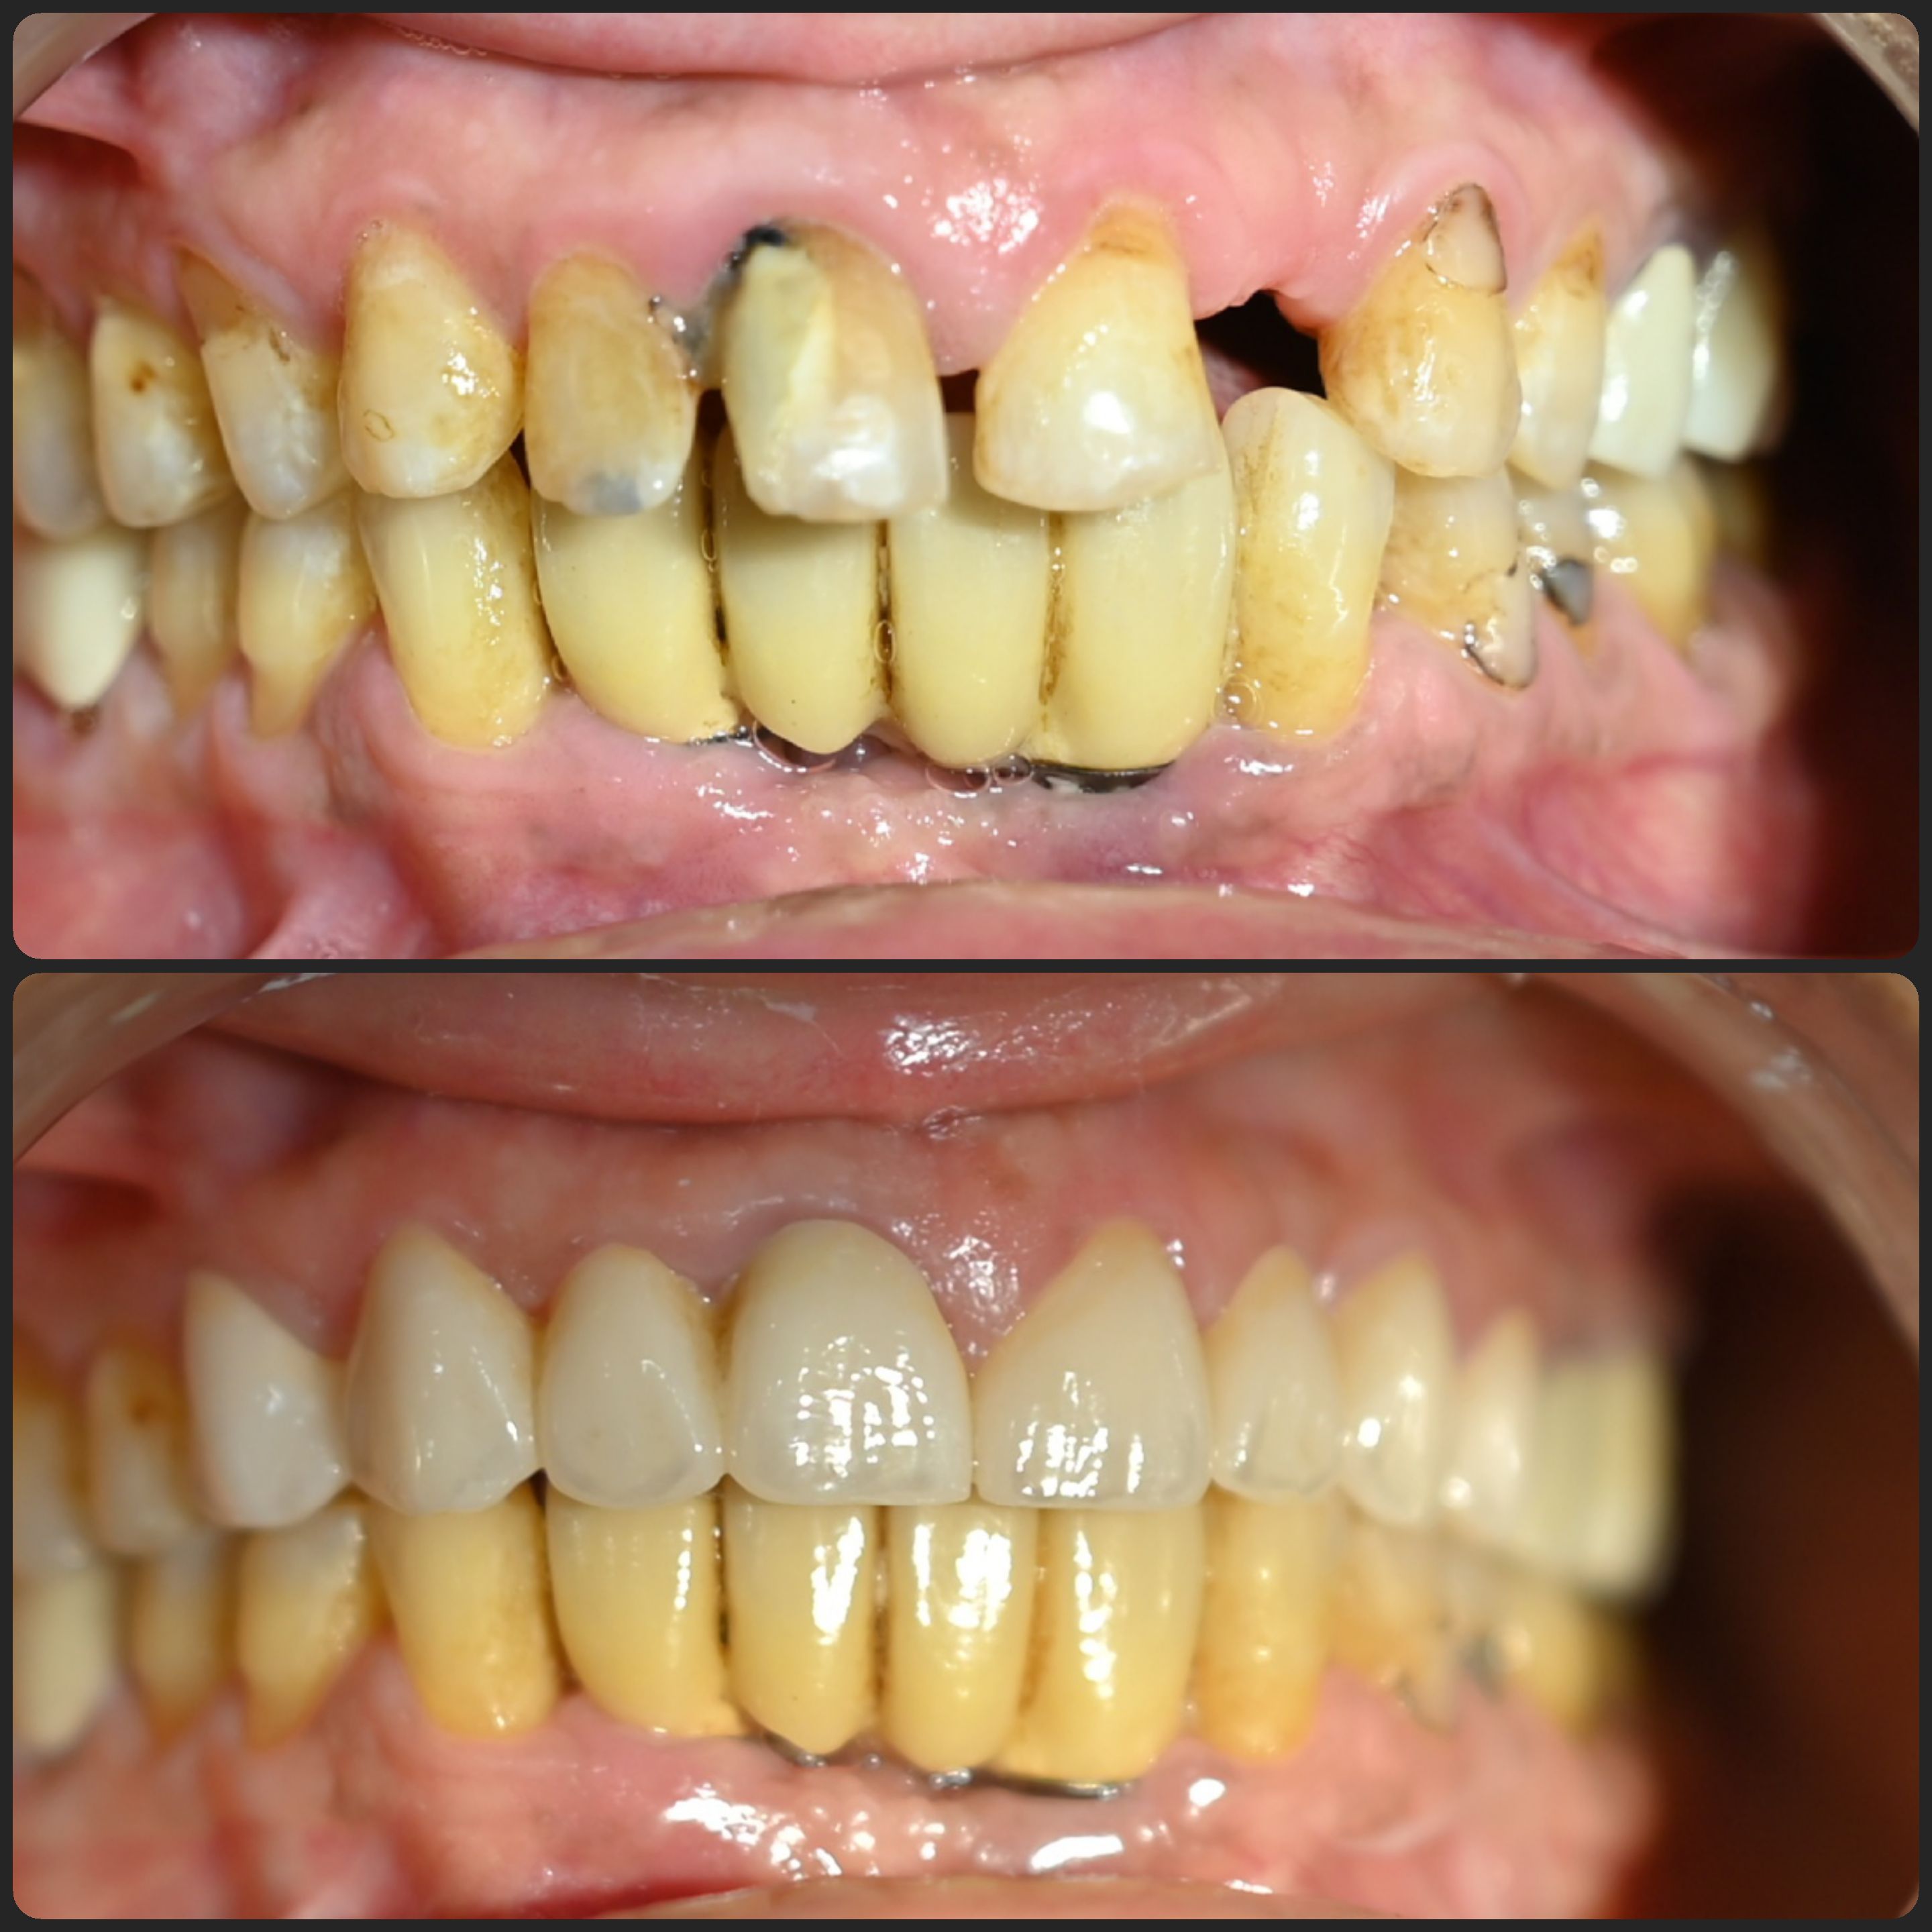

• Cases